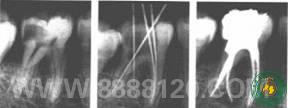

由于牙根根管的变异性大,为明确根管数目、形态、长度,了解根管充填后效果,保证根管治疗的顺利完成,常需在治疗前、中、后多次拍摄牙片。